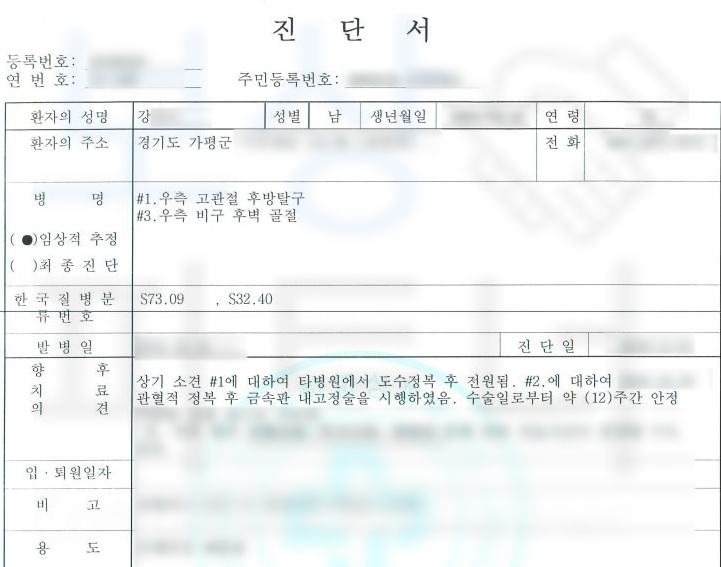

이 사고로 인해 재해자는

골반부의 고관절 후방 탈구 및

비구 후벽 골절 진단을 받으셨고 응급실에서 도수 정복 후 비구의 골절이 심한 상황이었기에 금속판 내 고정술을 시행하셨습니다.

전치 12주 진단받아 병원에 입원하며 요양을 하셔야 했죠. 산재 보험 처리와 개인적으로 가입해두신 보험에서도 추가 보상받을 수 있습니다. 보상 파트너가 말씀드리는 보상은 장해 보상만을 가리킵니다!